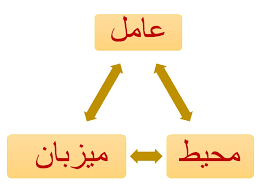

قیمت: 58٬000 تومان - دسته بندی فایل: علوم پزشکیپاورپوینت مثلث اپیدمیولوژی

فروش ویژه پاورپوینت حرفه ای مثلث اپیدمیولوژی با تخفیف استثنایی فقط 82225 هزار تومان تعداد اسلاید : 50 اسلاید